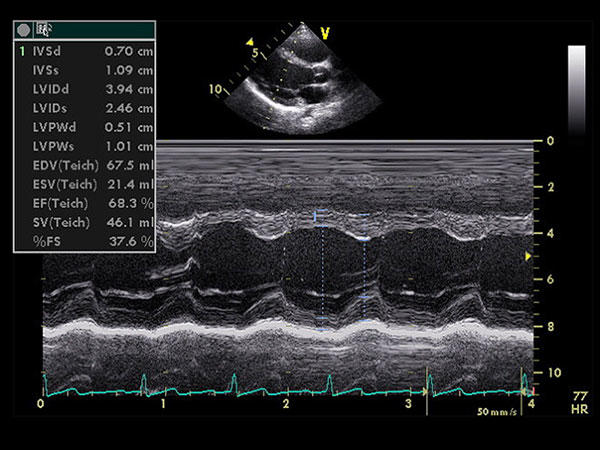

Ecocardiografía que muestra una medición del ventrículo izquierdo del corazón.

Evaluación de ecocardiografías

Este verano pasado, la DCP reunió a un grupo de médicos oncólogos y de especialistas en cardiología para revisar los resultados de ecocardiografías de pacientes que participaron en dos estudios de cardiotoxicidad apoyados por el NCI. Los estudios, que son financiados por el programa de oncología comunitaria del NCI, son el:

Por un análisis de estos dos estudios, los expertos empezaron a establecer un marco de trabajo para evaluar la cardiotoxicidad en estudios clínicos de cáncer futuros. Se llegó a un acuerdo general que, aunque una ecocardiografía es una herramienta aceptada y ampliamente disponible para medir la función cardíaca en general, se necesitaba más investigación para evaluar el uso de esta tecnología como herramienta de diagnóstico para resultados de cardiotoxicidad en pacientes que participan en estudios clínicos de cáncer.

Por ejemplo, el doctor Gregory T. Armstrong, del St. Jude Children´s Research Hospital, y sus colegas encontraron recientemente que la evaluación de la salud cardíaca mediante el uso de mediciones ecocardiográficas conocidas como deformación longitudinal global y función diastólica puede ayudar a identificar a los supervivientes del cáncer que tienen un alto riesgo de enfermedad cardíaca inducida por el tratamiento. Pero los autores del estudio advierten que se necesita investigación adicional para caracterizar los cambios cardíacos que ocurren en supervivientes adultos de cáncer infantil con el tiempo que pueden predecir la aparición de daño cardíaco.